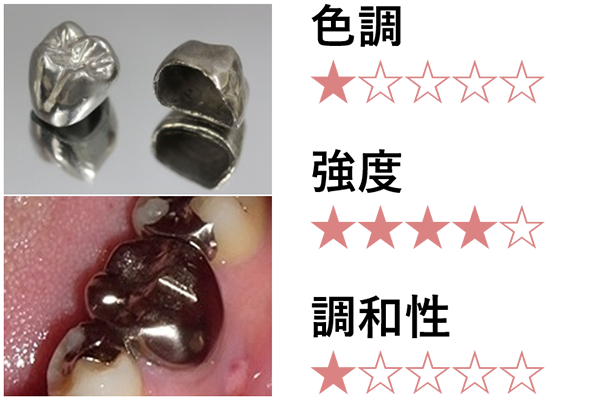

メタルクラウン

保険適用